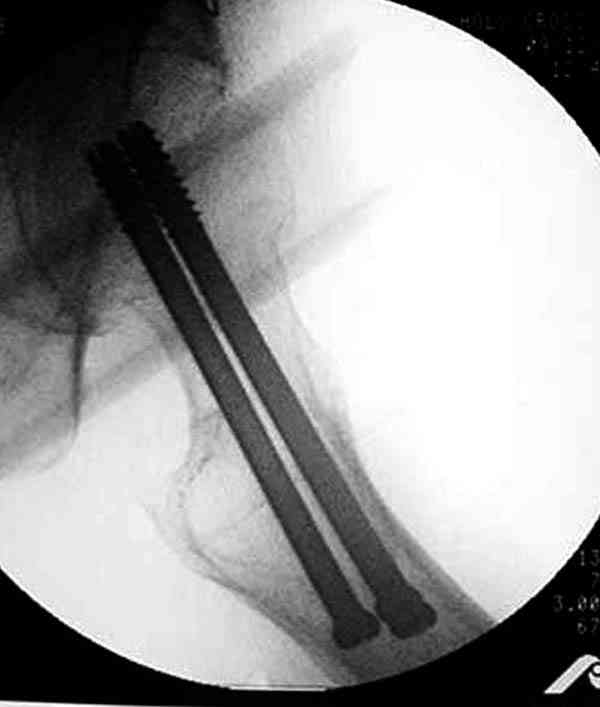

Коллега Челноков прав, здесь еще имеется риск перелома за счет ослабления латерального кортекса. Во время установки канюлированных шурупов за редким исключением спица вводится с одного раза, множественные попытки ослабляют латеральный кортекс, что станет источником перелома в этом месте.

Здесь случай перелома из-за ослабления латерального кортекса через 3 недели после операции на шейке. Шурупы были установлены под большим углом, слабый латеральный кортекс не выдержал нагрузку.